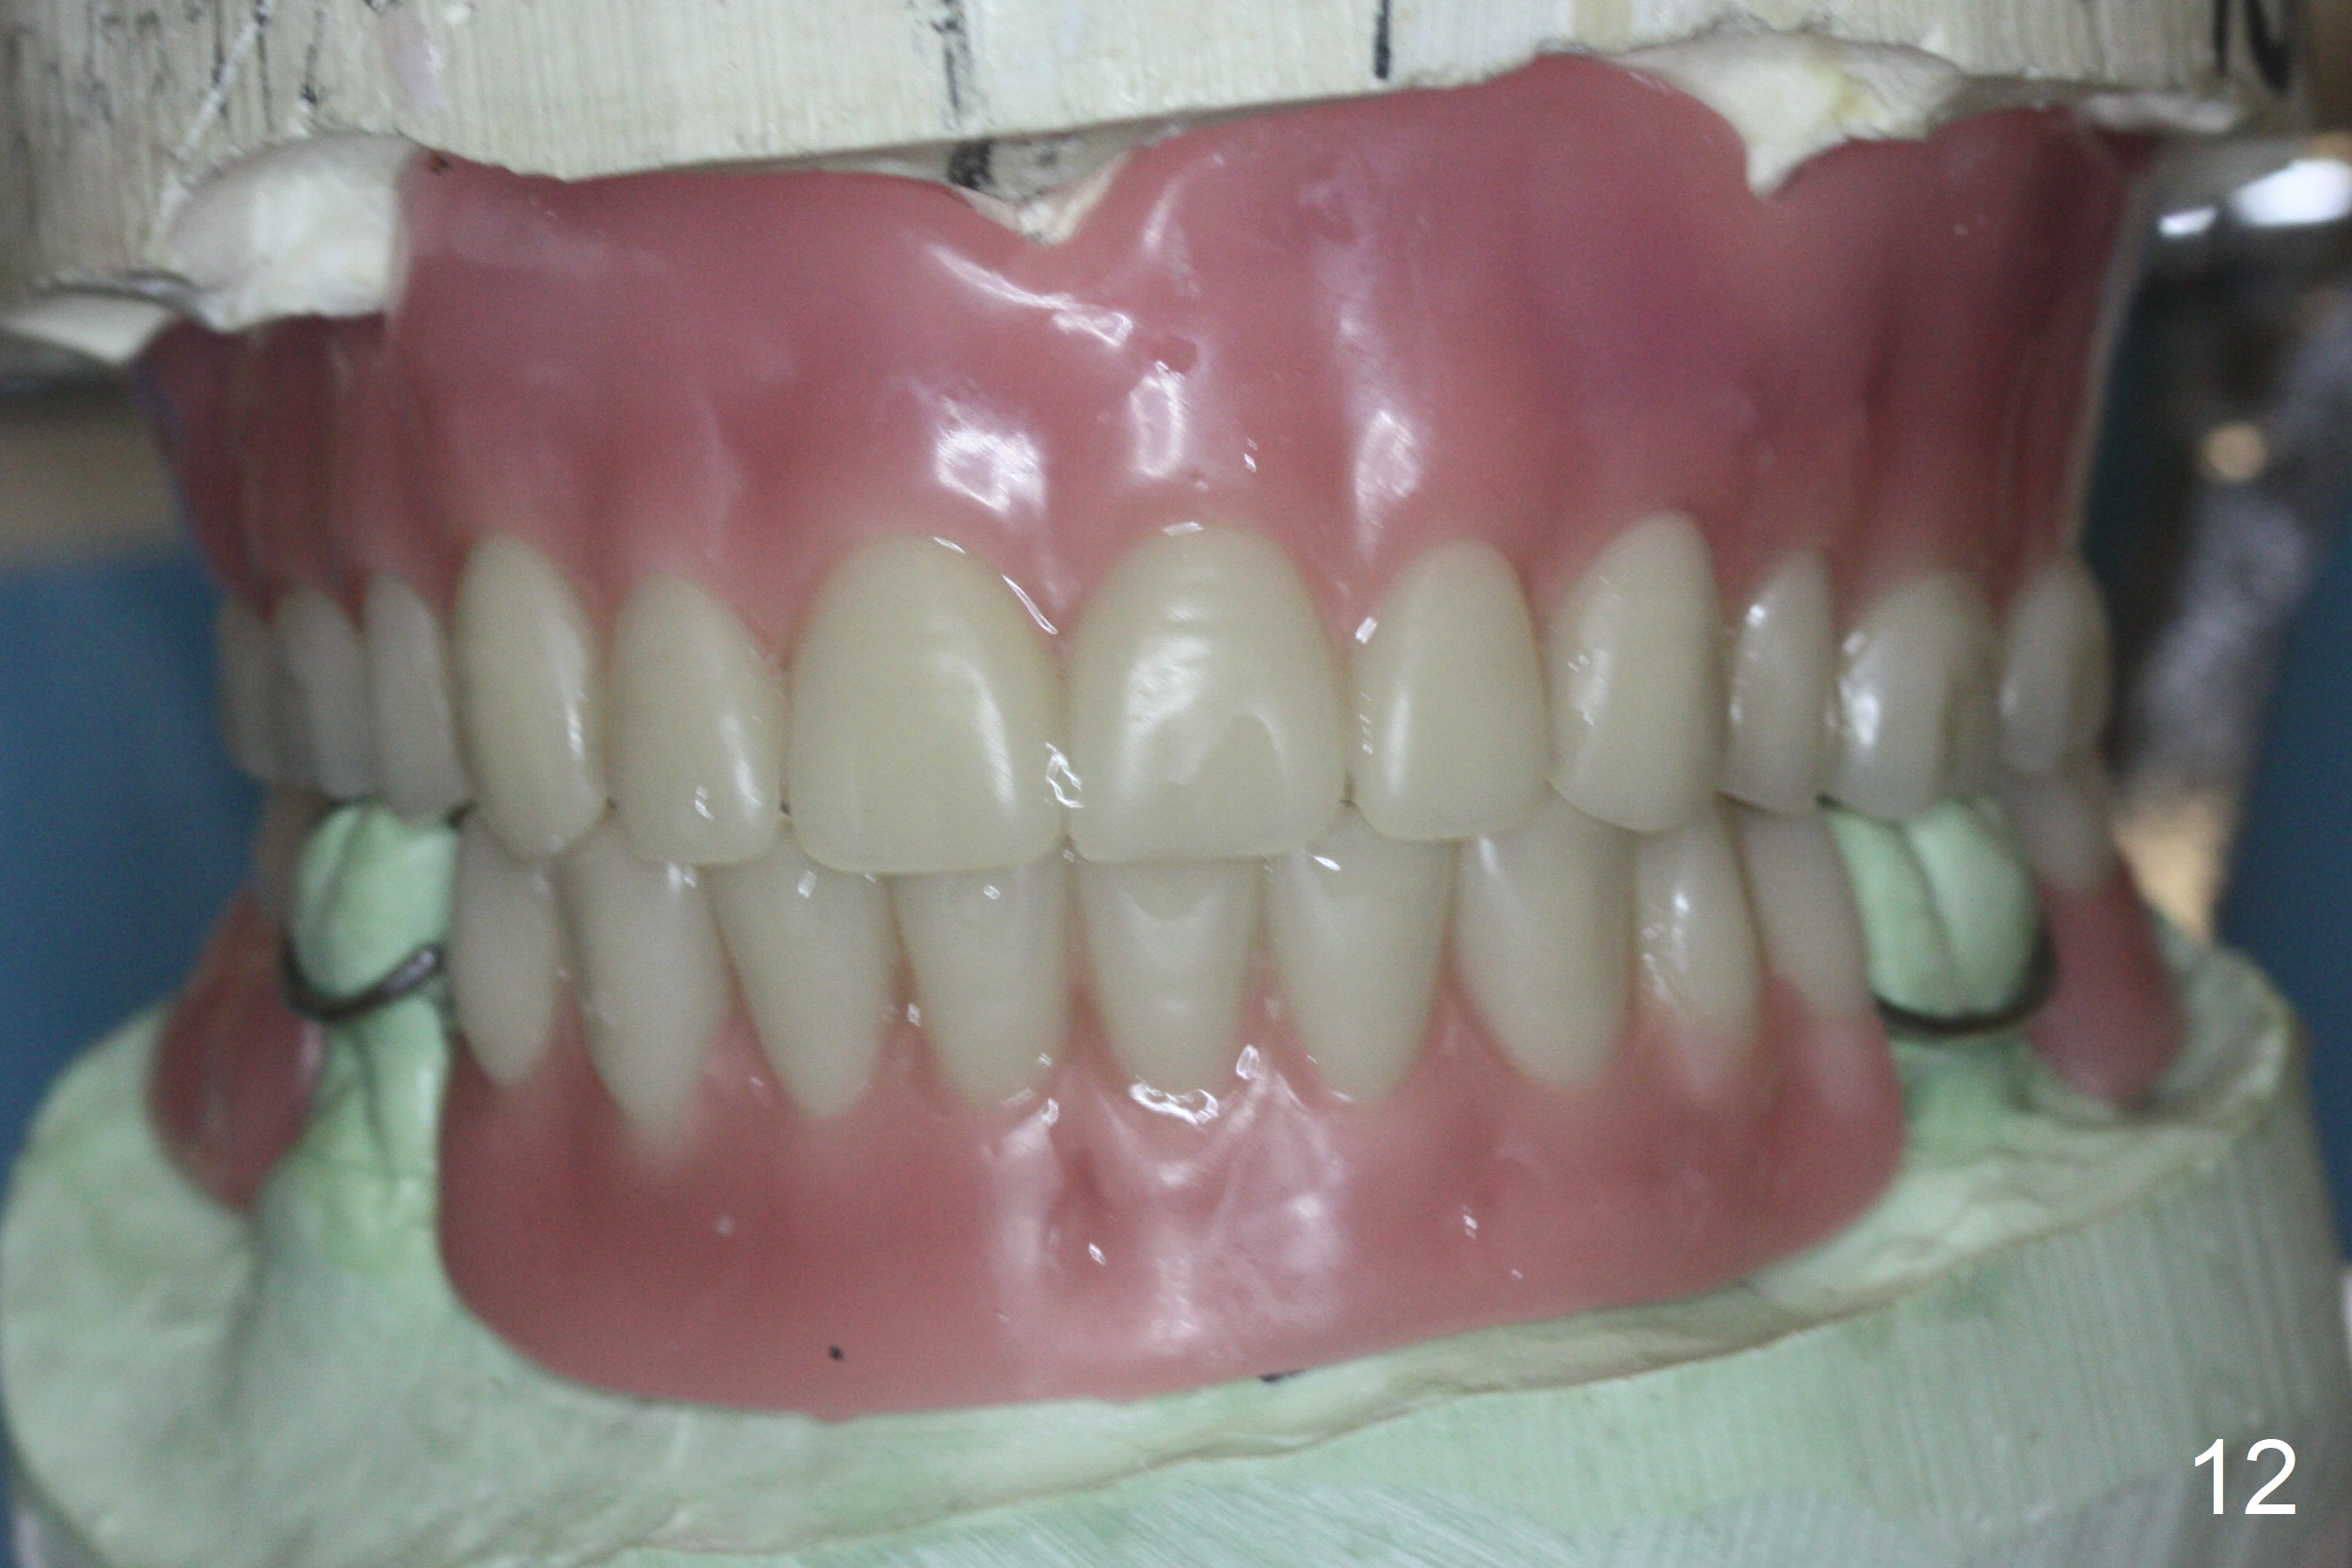

The implant osteointegrates 2 months postop (Fig.9). A pair abutment is placed (Fig.10: 5x4(2) mm) for a provisional (Fig.11). Wax up for final restorations (Fig.12-15). There is no bone resorption 1 year 4 months post cementation (Fig.16). The RPD is doing fine. The implant remains stable 3.5 years post cementation (in spite of open margin), while the other abutment for the RPD (the tooth #30) has mobility with gingival recession.